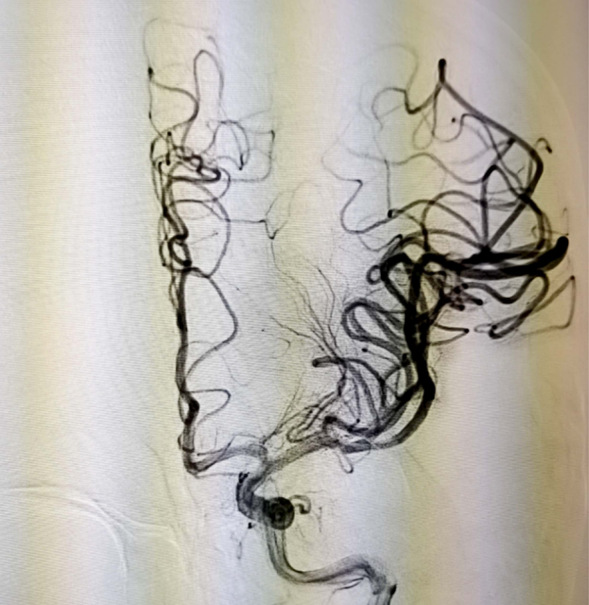

当天15点47分,一位老年男性患者在家中看电视时突发右侧肢体活动不灵,不能言语,家属紧急将其送往我院急诊就诊并联系神经内五科迟景宏主任。16点40分,患者在家属陪同下来到我院急诊。迟景宏主任在紧急查看患者病情并完善相关检查后,果断判断患者为急性大血管闭塞,通过与患者家属交代病情,征得了患者家属的同意,决定对其行静脉溶栓治疗。经验丰富的迟景宏主任判断单一溶栓难以缓解患者大血管闭塞所导致等症状,立即请介入放射科刘琳主任、莫庆国副主任进行会诊,建议桥接取栓。17点25分,患者顺利完成主动脉弓上脑血管造影证实左侧大脑中动脉下干闭塞。根据患者病情,神经、介入团队经商议后决定行BADDASS治疗,三件套组合:BGC+中间导管+长取栓支架,交换8F动脉鞘,引入BGC:8F×95cm;颅内支持导管:5F*125cm;取栓支架:4mm*20mm至远端病变血管,透视下释放取栓支架至病变血栓处,停留8分钟后取出大量血栓,一次取栓成功,达到三级再通。复查造影见左侧颈内动脉、左侧大脑前动脉、左侧大脑中动脉显影正常,血流改善,各分支显影良好,M1段未见明显狭窄,术中复查C臂CT未见颅内出血。19点10分,手术顺利结束,术后患者意识清楚,肢体活动较前明显改善,后经对症及康复治疗,患者于2月1日顺利出院,出院时患者恢复如常。通过医生的准确判断、过硬的医疗技术、团队的紧密配合,患者从入院到成功救治在150分钟内顺利完成。

术中取出血栓